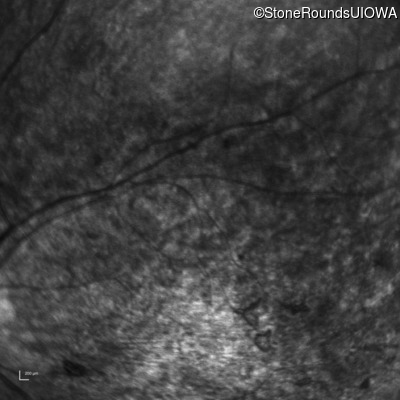

Infrared Fundus Photograph - Right - 20/400 sc

Exemplar

Infrared Fundus Photograph - Left - 20/250 sc